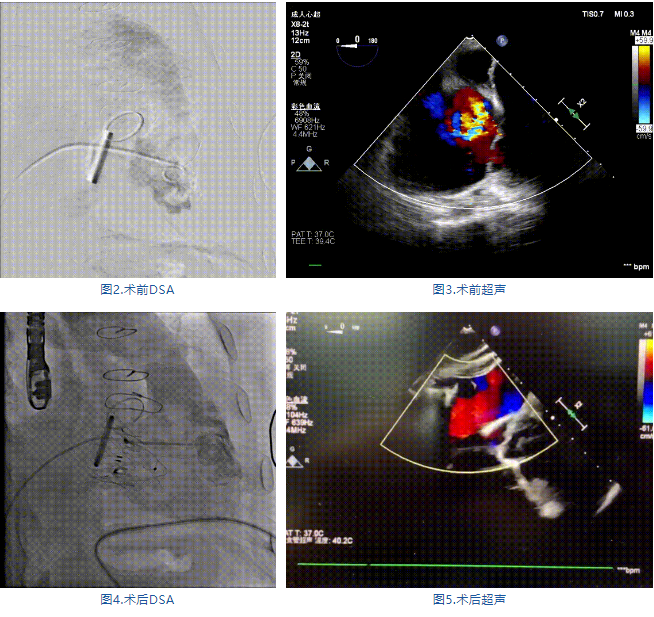

手術在全麻狀態下進行,郭惠明教授團隊采用經右側頸靜脈入路的方式送入輸送器進入體內,并在TEE和DSA的指引下進行。在輸送器進入右室后釋放室間隔錨定裝置,旋轉輸送器,使得錨定裝置對準室間隔面;而后釋放前瓣夾持件,確定夾持件位于右室側釋放LuX-Valve Plus人工瓣膜盤片,再使用DSA和超聲確認盤片是否位于右房側,同時調整瓣膜的同軸性。緊接著在DSA和超聲的監視下調整室間隔錨定件貼合室間隔,釋放室間隔錨定裝置。再次確認瓣膜的穩定性和同軸性后,將輸送器撤出體內,最終完成LuX-Valve Plus人工瓣膜植入(圖2-5),手術獲得圓滿成功。患者在手術室即刻拔除氣管插管,術后超聲提示LuX-Valve Plus人工三尖瓣瓣膜同軸性良好,瓣架固定牢靠,無反流和瓣周漏。